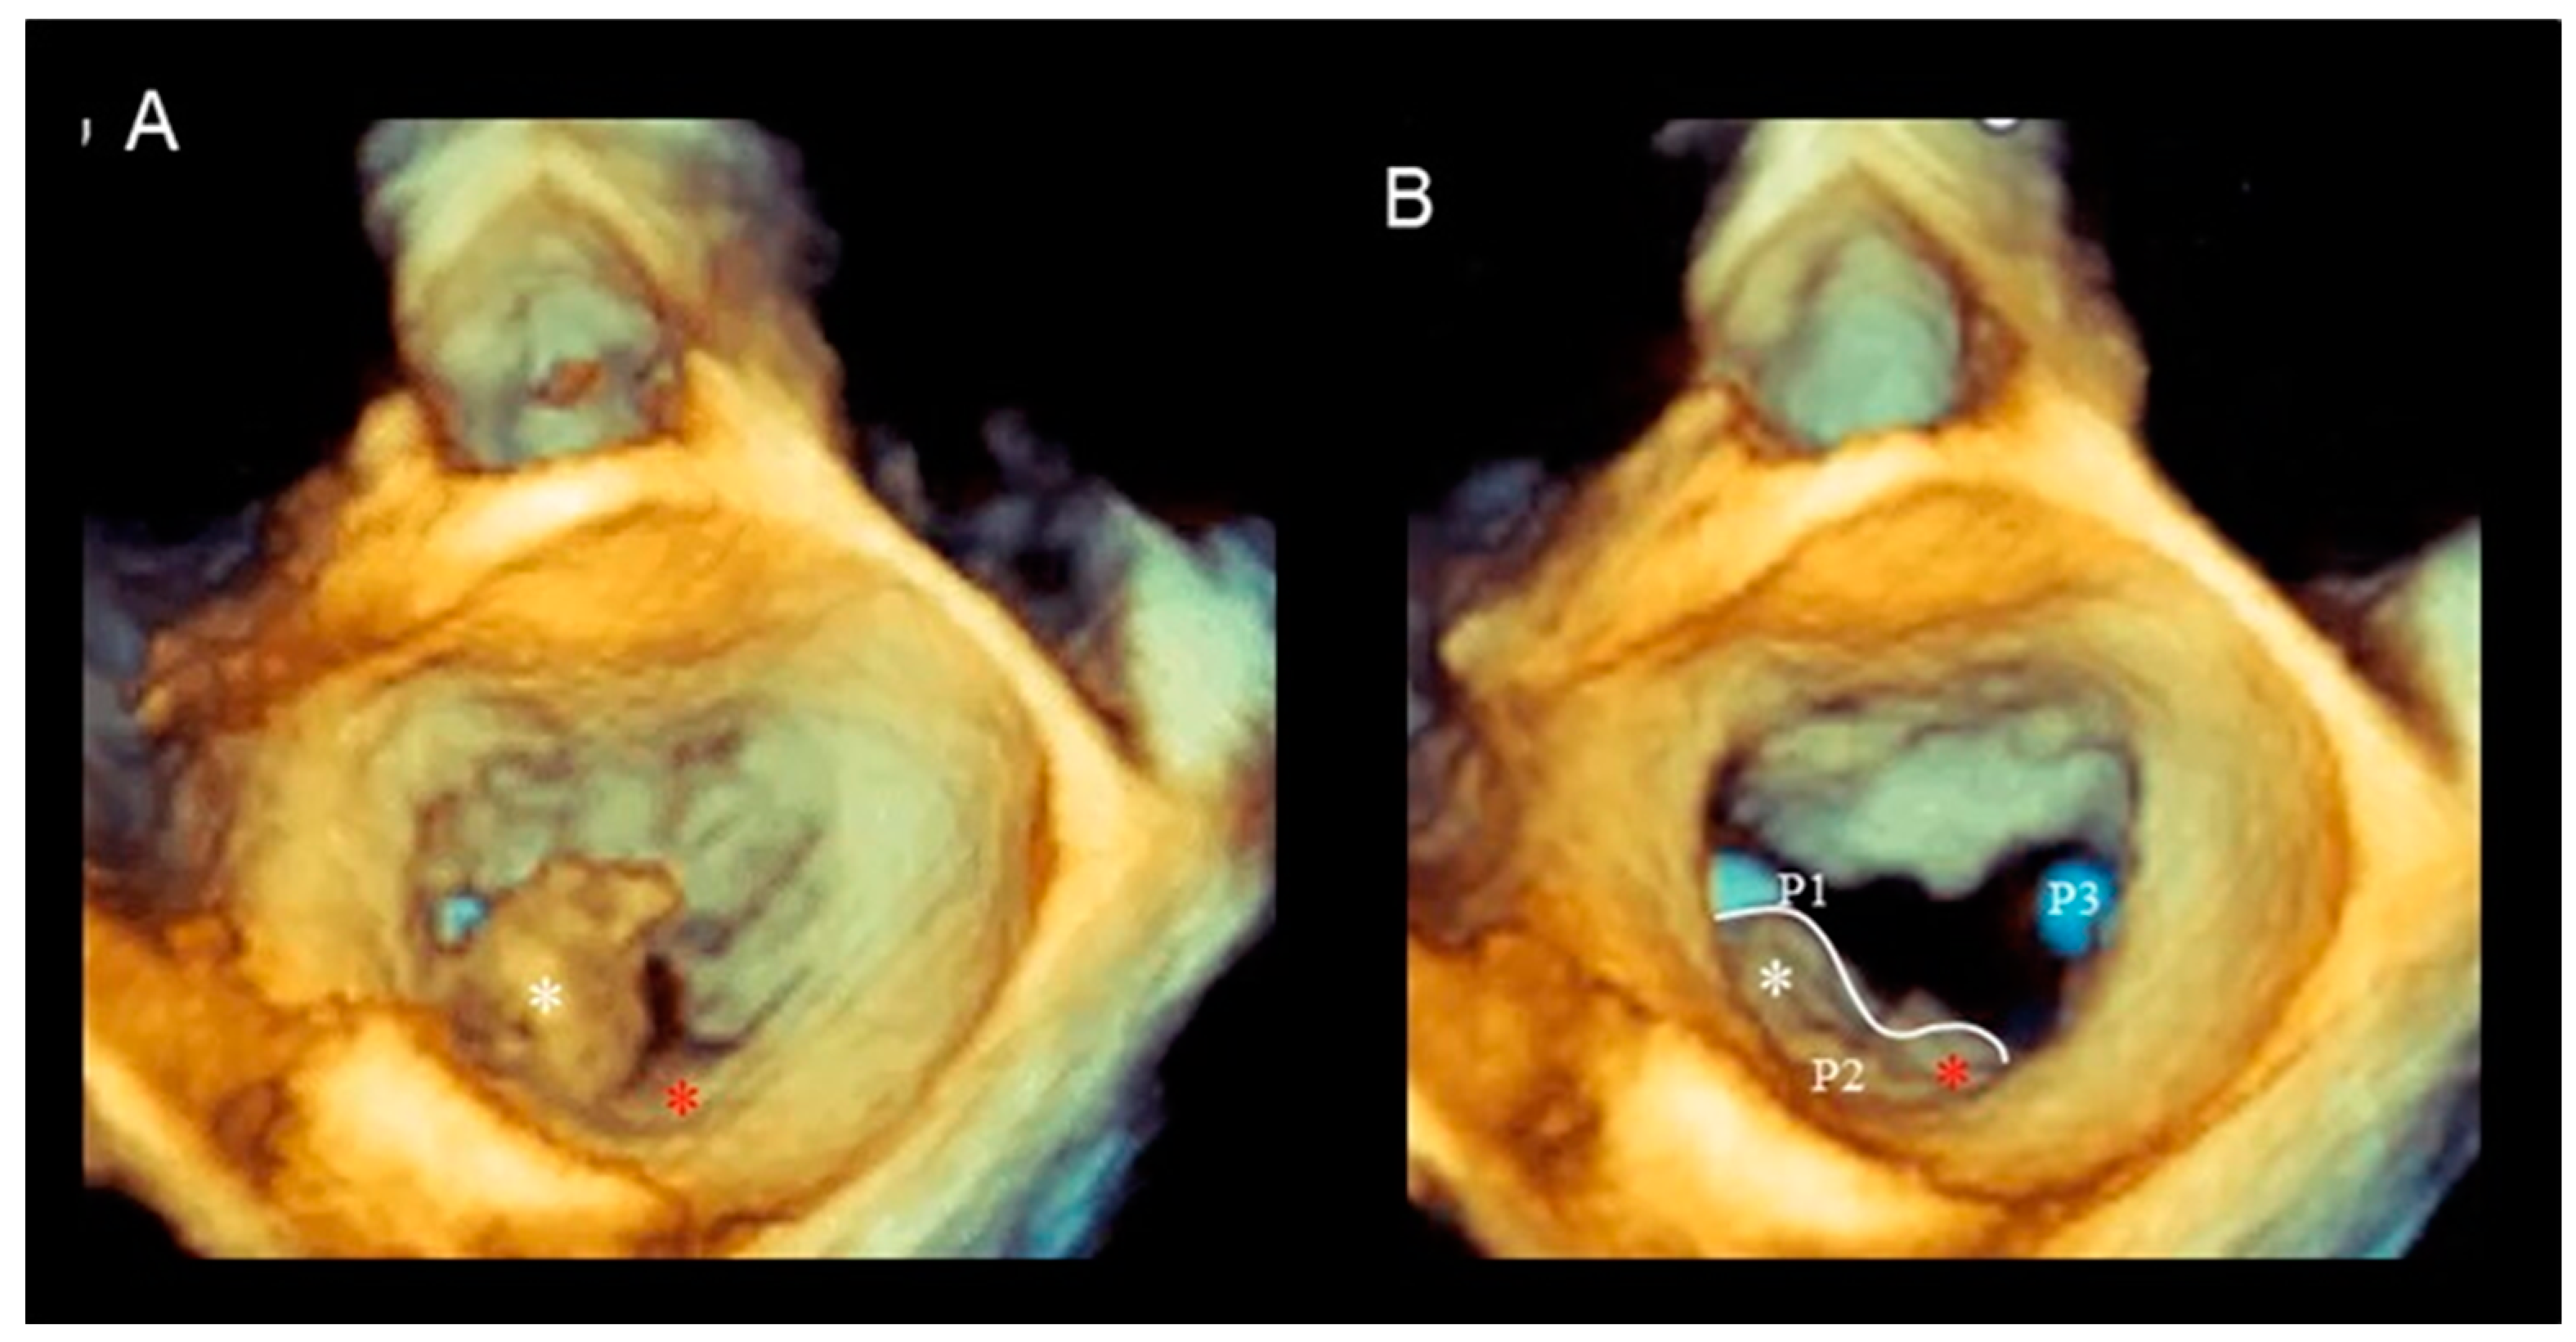

Cleft and Cleft-like Indentations

| Phenotype | Description | Image |

|---|---|---|

| Fibroelastic deficiency | This phenotype is characterized by a deficient production of collagen, elastin, and proteoglycans. Leaflets preserve their own three-layer arrangement, but upon surgical inspection, they appear fragile and translucent. The etiology of connective tissue deficiency in FED is unknown, but it has been suggested that it may be the result of an accelerated ageing process. The cause of regurgitation is the rupture of one or more primary chordae tendineae, which usually involves a single scallop. The figure shows a small P2 prolapse in an otherwise apparently normal MV. |  |

| Fibroelastic deficiency plus | This phenotype is characterized by a single scallop prolapse, but the involved scallop is redundant and affected by myxomatous degeneration. The remaining scallops are normal. Qualitative histological lesions in the prolapsed tissue of FED plus are similar to those of Barlow’s disease. It has been suggested that FED plus may be considered a sort of worsening stage of FED, leading to the hypothesis that the myxomatous changes could also be secondary to jet lesions. The figure shows a large P2 prolapse with ruptured chordae tendineae (arrows). |  |

| Forme fruste | In this phenotype, the entire posterior leaflet is redundant and is affected by myxomatous degeneration, while the anterior leaflet is macroscopically and histologically normal. It can be speculated that this phenotype is an incomplete form of Barlow’s disease. The figure shows multiple prolapses (asterisks) of the posterior leaflet. |  |

| Barlow’s disease | Barlow’s disease is the result of an abnormal accumulation of myxomatous substances (mainly proteoglycans) in the spongiosa layer, and a simultaneous disruption of collagen fibers in the fibrosa layer. As a consequence, the three-layered arrangement of the leaflets is lost. The characteristic macroscopic appearance, either in pathological specimens or in the operating room, is that of a thick, bulky, redundant leaflet, elongated chordae tendineae, and annular dilatation. The excess leaflet tissue leads to the displacement of both leaflets beyond the annulus, with a lack of coaptation and consequent MR. The figure shows an example of Barlow’s disease seen from a tangential view largely protruding into the left atrium. LAA = left atrial appendage, AML = anterior mitral leaflet; PML = posterior mitral leaflet. |  |